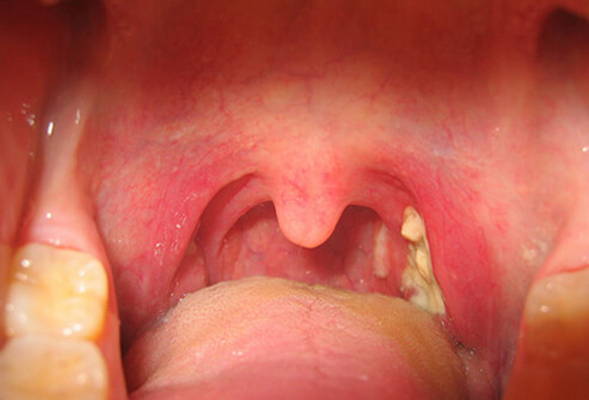

扁桃體週膿腫圖片